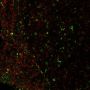

Functional studies (published)|Flow, surface (verified)|IF (verified)|IHC, frozen (verified)

Flow (surface) (verified)|IF (verified)|IHC (frozen) (verified)

Higher concentration may be required for direct detection using primary antibody conjugates than for indirect detection with secondary antibody|Immunofluorescence (direct conjugate): 1-5 ug/mL|Flow Cytometry 0.5-1 ug/million cells/0.1 mL|Does not react with Macaca mulatta (rhesus monkey), others not tested|Optimal dilution for a specific application should be determined by user